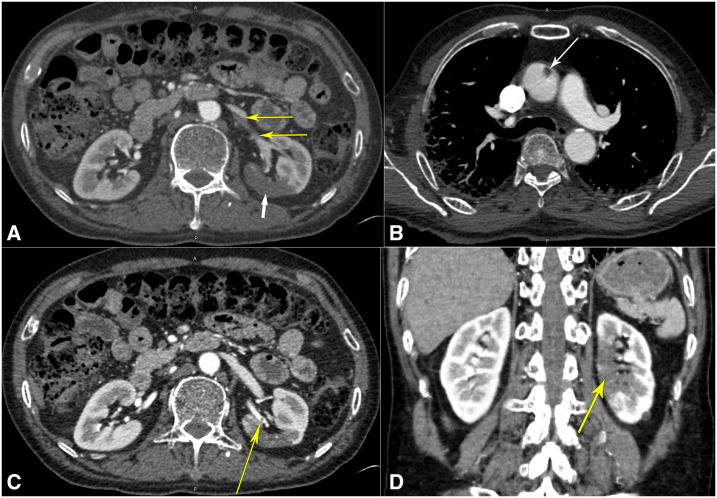

Figure 2.

Computed tomogram with angiography. (A) Computed tomography angiogram of the abdomen showing left superior renal artery thrombi (thin yellow arrows) with infarcts in the posterior mid-pole of the left kidney (thick white arrow). (B) Computed tomography angiogram of the thorax showing the ascending aortic thrombus (arrow). (C) Computed tomography angiogram of the abdomen showing another view of the left superior renal artery thrombus (yellow arrow). (D) Computed tomography angiogram of the abdomen in the coronal view revealing the extent of the left renal infarction (yellow arrow). This figure appears in color at www.ajtmh.org.

However, he was readmitted 2 days later with worsened hypoxia. Vitals revealed he was afebrile at 98.9°F (37.1°C), blood pressure was 134/80 mmHg, tachycardic with a pulse of 112/minute, tachypneic at 34 breaths/minute, and hypoxic to 88% on 4 L/minute of oxygen via NC. Examination still noted bilateral crackles in all lung fields. Repeat investigations revealed positive COVID-19 test, persistent absolute lymphopenia, and further elevation of D-dimer, LDH, ferritin, and CRP (Table 1). A repeat chest X-ray showed worsened bilateral patchy opacities (Figure 1B). Saturations improved to 92% on 6 L/minute of oxygen supplementation. Hydroxychloroquine therapy was discontinued because of elevated QTc of 505 milliseconds. With worsening COVID-19 pneumonia, we initiated methylprednisolone 40 mg intravenously twice daily, along with lopinavir–ritonavir 400–100 mg orally twice daily and enoxaparin 40 mg subcutaneously twice daily. A computed tomography–pulmonary angiogram was negative for pulmonary embolism (PE) but revealed extensive multi-lobar ground-glass opacities (Figure 1C). Because of persistent dyspnea and hypoxia in the next 2 days, he was intermittently proned while on 6 L/minute oxygen via NC, and maintained saturation of 90–92%. Laboratory parameters were repeated intermittently as noted in Table 1. On day #9 since initial presentation, the patient complained of sharp left iliac fossa and left flank pain, which was high grade (8/10), constant, and radiating to his back, associated with nausea but no vomiting, diarrhea, dysuria, hematuria, fever, chills, or rigors. Urinalysis revealed clear, straw-colored, non-bloody urine with 30 mg/dL protein. An urgent computed tomography angiogram (CTA) revealed left superior renal artery thrombi with infarcts in the posterior mid-pole of the left kidney (Figure 2A, C, and D). The CTA also revealed ascending aortic thrombus (Figure 2B). Bilateral lower extremity ultrasound was negative for deep venous thrombosis (DVT). We initiated heparin intravenous infusion for therapeutic anticoagulation and discontinued enoxaparin. A loading dose of clopidogrel 300 mg was given and continued with 75 mg daily. On surgical review, no intervention was advised. The next day, the abdominal pain had resolved, but we discontinued lopinavir–ritonavir as the hepatic enzymes were rising. The oxygen requirement decreased to 4 L/minute by day #12 since presentation, and we switched to apixaban 5 mg orally twice daily for anticoagulation. The patient continued to steadily recover, with improving inflammatory and renal markers (Table 1). The urine output and electrolytes remained normal throughout (Table 1). By day #14 since initial presentation, the patient was with a saturation of 90% on room air at rest, only requiring supplemental oxygen on mobilization, and corticosteroids were discontinued. The next day, he was discharged home with home oxygen therapy and 3 months of apixaban and clopidogrel regimen.